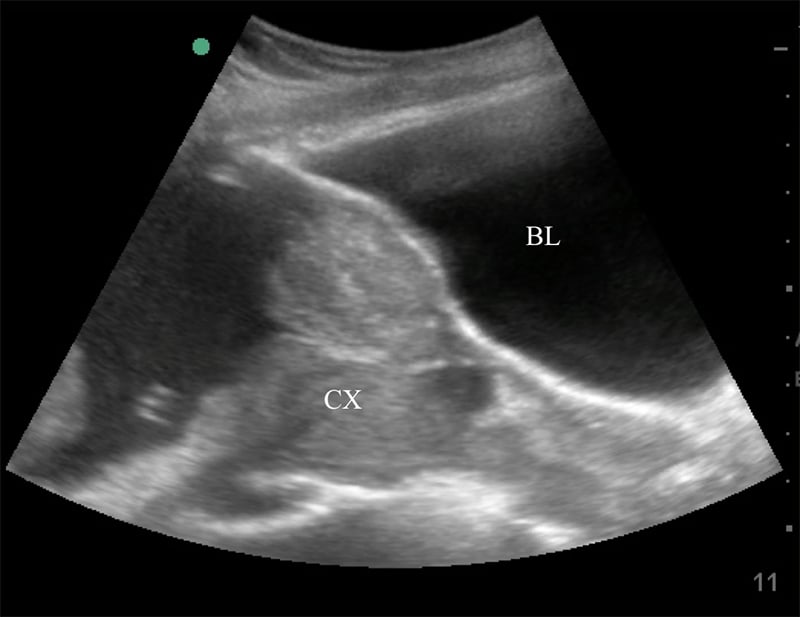

- Placentation

- Abnormal placentation such as placenta previa increases the risk of peripartum maternal hemorrhage.27

- Detecting abnormal placentation prior to delivery may allow preparation for increased hemorrhage or operative delivery and lower risk to the mother.

- Placenta previa (covering the internal cervical os) or low-lying placenta (within 2 cm but not covering the cervical os) should be confirmed by transvaginal US if available.

Figure 35. Sagittal transabdominal view of the pelvis revealing the anechoic urinary bladder (BL) and a normal cervix (CX) just below.

Figure 36. Sagittal transabdominal view of the pelvis similar to Figure (prior), with hyperechoic placenta (PL) covering the internal cervical os (CX).